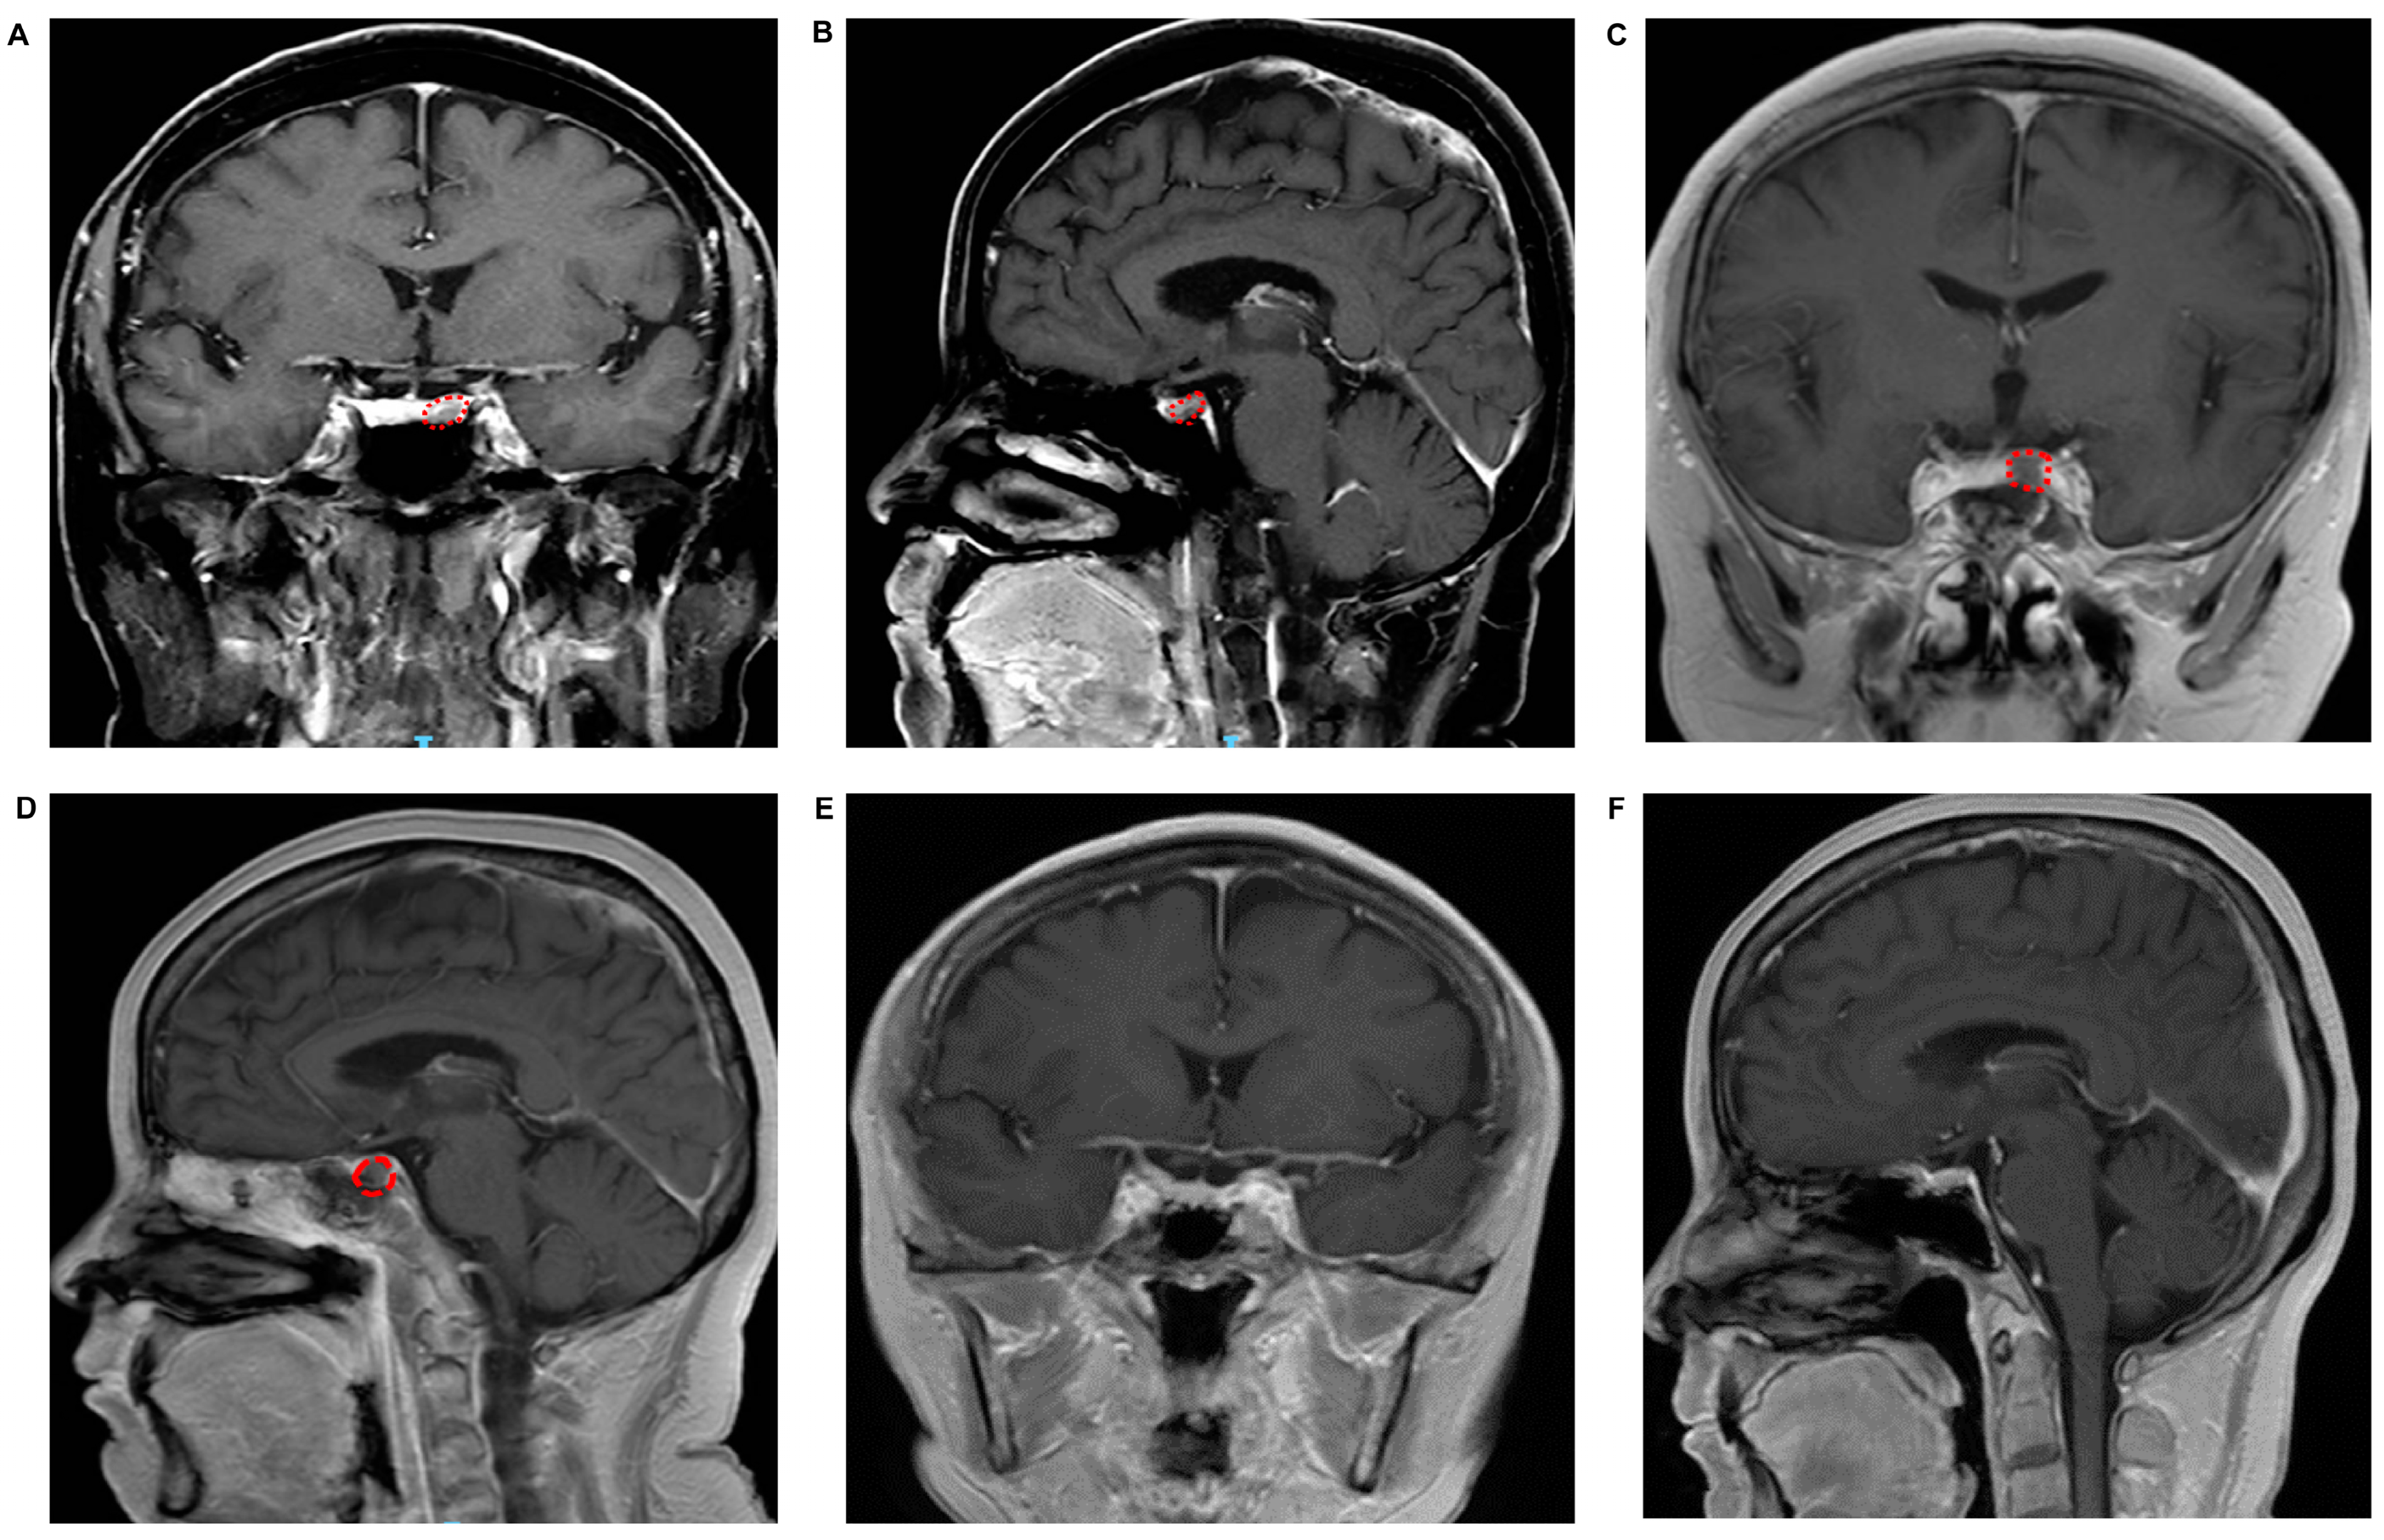

2. Materials and Methods

3. Results